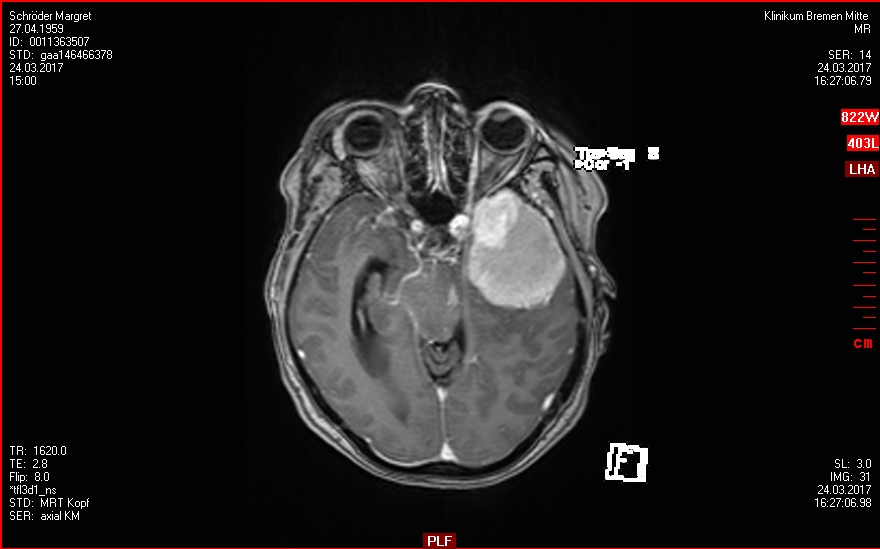

30.03.2017

OP - Krankenhaus Bremen-Mitte

Neurochirugie

Resektion des Keilbeinflügelmeningeoms links